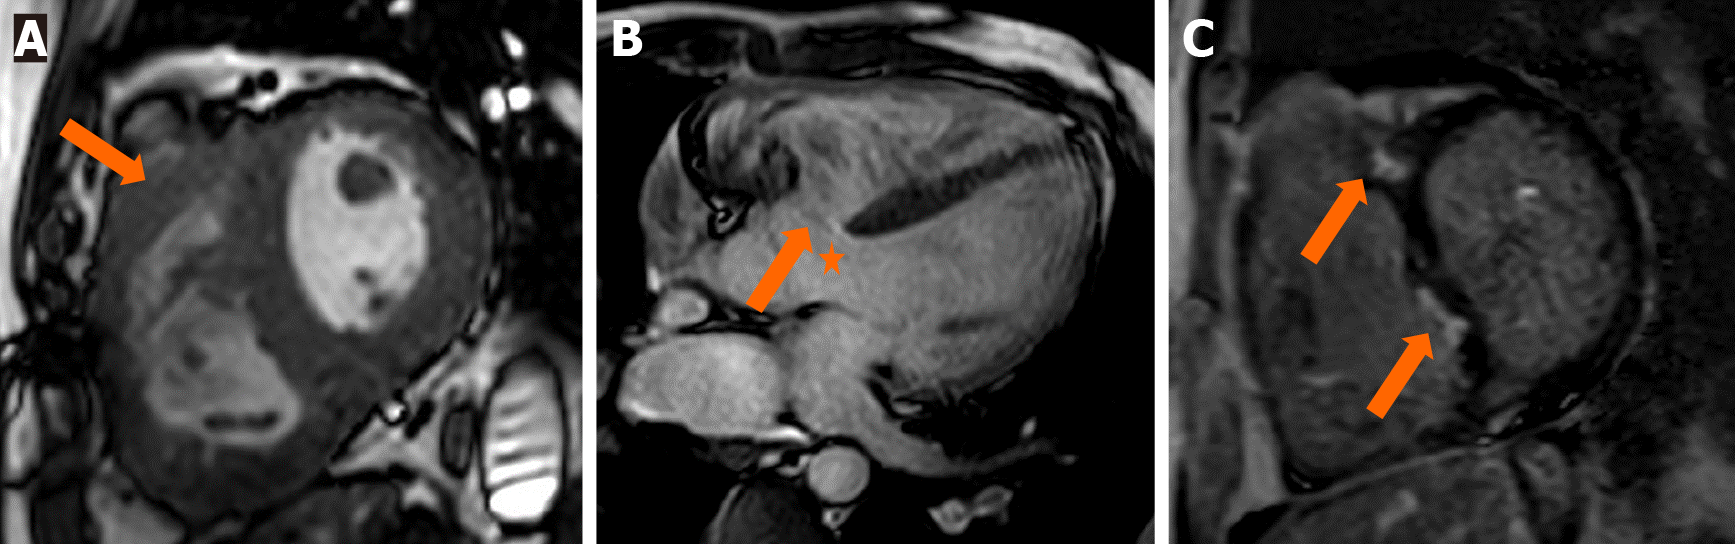

CMRI criteria have been proposed to help in the decision-making process regarding PVR[24]. Recent guidelines recommend PVR in symptomatic patients with moderate–severe PR with RV dilation or RV dysfunction[25,26]. Other associated valvular abnormalities, if present, should also be identified for proper intervention. Tricuspid regurgitation is commonly seen in these patients. Accurate grading of the TR can be done using MRI. Aneurysm of the RVOT, which is manifested as the dyskinetic movement of the RVOT wall (or outward movement during systole), should be carefully seen, as it is an independent predictor of RV dysfunction and arrhythmia development[27,28]. Late gadolinium enhancement can identify scars in vascular territories in patients with ischemic cardiomyopathy (Figure 4). Dilatation of other cardiac chambers should also be assessed, including atrial enlargement, which serves as an outcome predictor.

Figure 4

Figure 4 Cardiac magnetic resonance imaging in an operated patient of tetralogy of Fallot. A: Short-axis view showing a dilated right ventricle (RV) with thickened walls; B: Perimembranous ventricular septal defect (asterisk) with regurgitant jet (block arrow) across the tricuspid valve, suggestive of regurgitation; C: Focal areas of late Gadolinium enhancement in the RV and RV side of the septum.